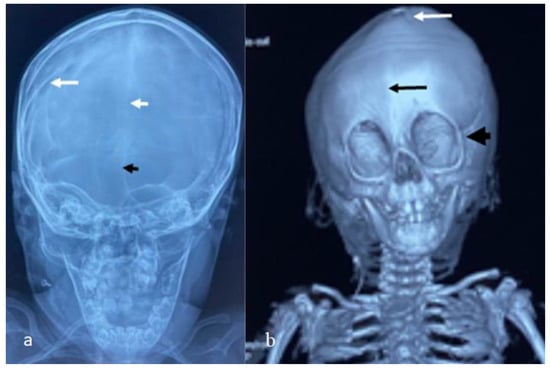

For this syndrome, we clinically investigated two unrelated affected boys. The first was a one-month-old boy presenting with multiple contractures who was falsely diagnosed in other institutes as having positional plagiocephaly associated with idiopathic multiple contractures. A clinical examination at the age of one month showed growth deficiency (-2SD) and OFC (around the 75th percentile). Clinically, he manifested an abnormal craniofacial contour with prominent sloping of the frontal area. The helices were over-folded. The palpation of the skull gives the impression of a newly formed ridge along the metopic suture and a newly formed ridge along the sagittal suture, with a feeling of a rudimentary anterior fontanelle (the skull is elongated from front to back). The musculo-skeletal examination showed ligamentous hyper laxity but not hypotonia. Multiple contractures over the upper and lower limbs were, respectively, associated with multiple dislocations (hips and knee joints). Skeletal survey: a general skeletal radiograph at the age of one month showed multiple malformation complex, starting from the skull and extending downwards to involve the upper and lower limbs, respectively. The skull showed an apparent synostosis of the metopic suture. The upper limbs and lower limbs were notably associated with multiple dislocations (hips, wrists, knees and ankle, in addition to camptodactyly at the interphalangeal joints). The limb abnormalities were diagnostically important, in that there was a complete anterior dislocation of the tibia and fibula, and the patellae were absent (Figure 1a). A sagittal cranial CT scan showed craniosynostosis of the metopic suture associated with a well- formed ridge spreading from the metopic suture to involve the anterior portion and the posterior part of the sagittal suture, associated with the obliteration of the anterior fontanelle, with the eventual development of scaphocephaly (Figure 1b). The second child is a 12-month-old-boy- presenting with multiple dislocations on top of a malformative craniosynostosis. He manifested apparent craniofacial dysmorphic features (facial asymmetry, proptosis, depressed nasal bridge, long philtrum and a low set malformed ears). An AP skull radiograph at the age of 12 months showed an early closure of the metopic (black arrow head) and sagittal sutures (white arrow head) and partial closure of the right coronal suture (white arrow), leading to the development of skull–crown asymmetry. A 3D reconstruction CT scan of the same child at the age of 14 months showed a well-defined palpable bony ridge (black arrow) extending from the metopic suture upwards to include the sagittal suture (white arrow) (Figure 2a). Note that the extremely large orbital cavities (arrowhead) with diffuse early closure of the metopic and the sagittal sutures (arrow), leading to the development of a dysmorphic and asymmetrical contour of the head because of the unilateral upward bulging of the crown (white arrow). Asymmetrical contour of the cranium resulted from the unilateral partial closure of the right coronal suture and simultaneous but asymmetrical early closure of the squamosal sutures (Figure 2b). A 3D reconstruction CT scan showed the disproportion in growth between the cranial and facial bones. The apparent closure of the metopic and sagittal sutures led to the development of scaphocephaly. Interestingly, there was a unilateral early closure of the right coronal (white arrow) and early closure of the squamosal sutures, respectively (black arrow), causing the development of asymmetrical bulging of the central part of the crown (Figure 3a). A 3D reconstruction confirmed the persistence of the left coronal suture (arrow—Figure 3b). Chromosomal karyotyping and the FISH test were normal, and there were no disease-causing copy number variations (CNV) using array-CGH analysis.

Figure 2. AP skull radiograph at the age of 12 months-old-boy- showed early closure of the metopic (black arrow head) and sagittal sutures (white arrow head) and partial closure of the right coronal suture (white arrow), leading to development of skull–crown asymmetry. Three-dimensional reconstruction CT scan of the same child at the age of 14 months showed a well-defined palpable bony ridge (black arrow) extending from the metopic suture upwards to include the sagittal suture (white arrow) (a); Note that the extremely large orbital cavities (arrowhead) with diffuse early closure of the metopic and the sagittal sutures arrow), leading to the development of a dysmorphic and asymmetrical contour of the head because of the unilateral upward bulging of the crown (white arrow). Asymmetrical contour of the cranium resulted from the unilateral partial closure of the right coronal suture with the simultaneously but asymmetrical early closure of the squamosal sutures (b).